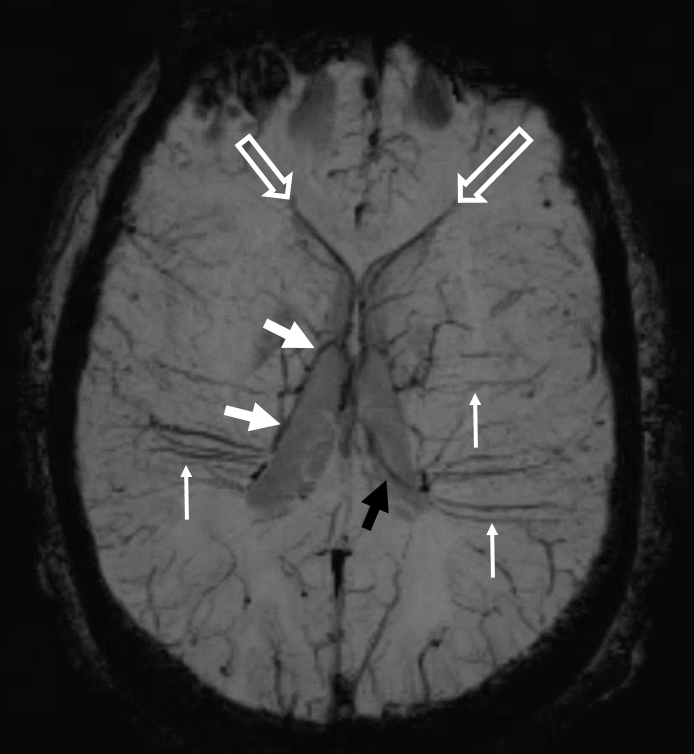

Another compensation for hypoplasia of the SSS is shift of superficial drainage into the deep venous system via the medullary veins draining into the internal cerebral veins. Courtesy Dr. Gopi Nayak. There is hypoplasia of the Superior Sagittal Sinus.

As one way of compensation for this superficial venous system deficiency, there is more venous drainage routed to the deep system. Amazing images of deep medullary/transverse venous prominence — completely nonpathologic, simply reflecting a shift of drainage equilibrium towards the deep venous system

Some arrows. Open white arrows — septal veins on the medial aspect of frontal horn. Thick white arrows — longitudinal caudate venous arcade. Black arrow — direct lateral vein, prominent because of hypoplasia of the posterior segment of the left longitudinal caudate vein. Thin white arrows are transverse/ medullary veins